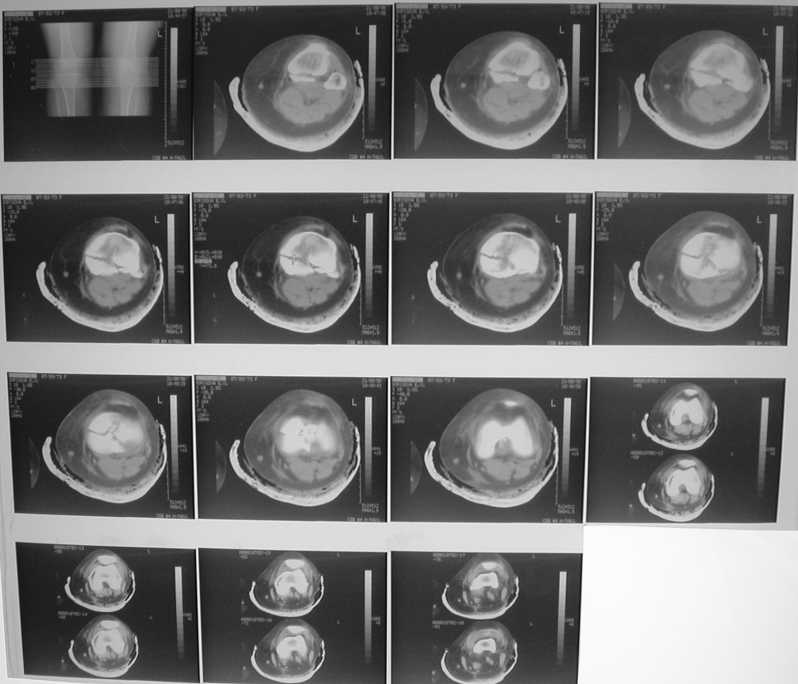

Проблема тут, видимо, не в выборе имплантата, а в том, что надо делать остеосинтез задним доступом. А пластинка подойдет практически любая - небольшая T-образная, хоть две 1/3 трубчатых. Угловая стабильность необязательна. Лишь бы трансплантат не вываливался. На КТ хорошо бы увидеть еще и срезы в сагиттальной и фронтальной плоскостях.

Каково состояние задней крестоообразной связки по УЗИ?

Если целая я советовал бы ограничиться минимальным объемом вмешательства - компрессионные винты спереди. Только надо

тщательно подобрать размер и винтов и их резьбовой части.

При повреждении задней крестообразной связки - ревизия из заднего доступа, обычно фрагмент с основанием достаточно большой и его можно

зафиксировать двумя винтами. Если же надо восстанавливать связку - можно из этого-же небольшого заднего доступа и отломок "привязать" протезом.

Этой фиксации достаточно, срастется. "Tomofix" мне представляется здесь избыточной, а сзади еще

ставить муторно.